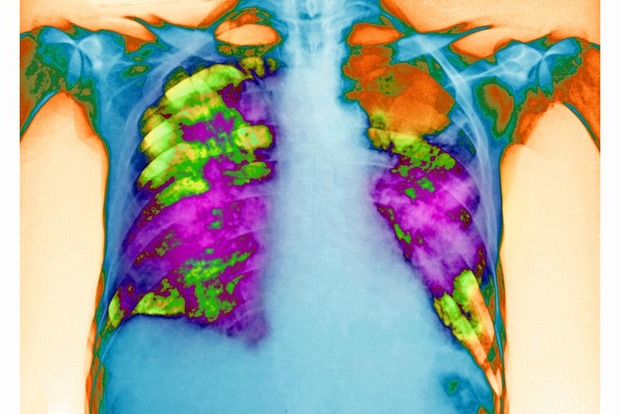

Entre 400 et 600.000 personnes, non dépistées pour certaines, souffrent de broncho pneumopathie chronique obstructive (BPCO) en Belgique. Dans 90 à 95% des cas, le tabac est en cause, a indiqué mercredi Thierry Webert, chef du service pneumologie au CHR de la Citadelle de Liège, à l'occasion du premier challenge national Vélo de la revalidation pulmonaire.